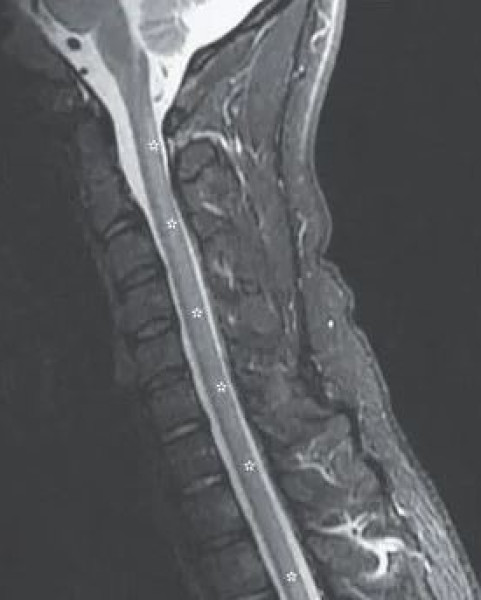

وكشف فحص التصوير بالرنين المغناطيسي أن الحبل الشوكي بدأت تظهر عليه علامات حالة عصبية تعرف باسم اعتلال النخاع، والذي يحدث أحيانا بسبب نقص فيتامين B12، ويحدث هذا عندما يتم ضغط الحبل الشوكي بسبب الالتهاب في المناطق المحيطة.

وإذا ترك دون علاج، يمكن أن يؤدي اعتلال النخاع إلى تلف كبير ودائم في الأعصاب بما في ذلك الشلل وحتى الموت، حيث وجد الأطباء أيضا أن جزءا من النخاع الشوكي، والعمود الظهري، المسؤول عن الشعور باللمس، قد أصيب بجروح بالغة، وكشفت الفحوصات عن وجود آفة متطورة.